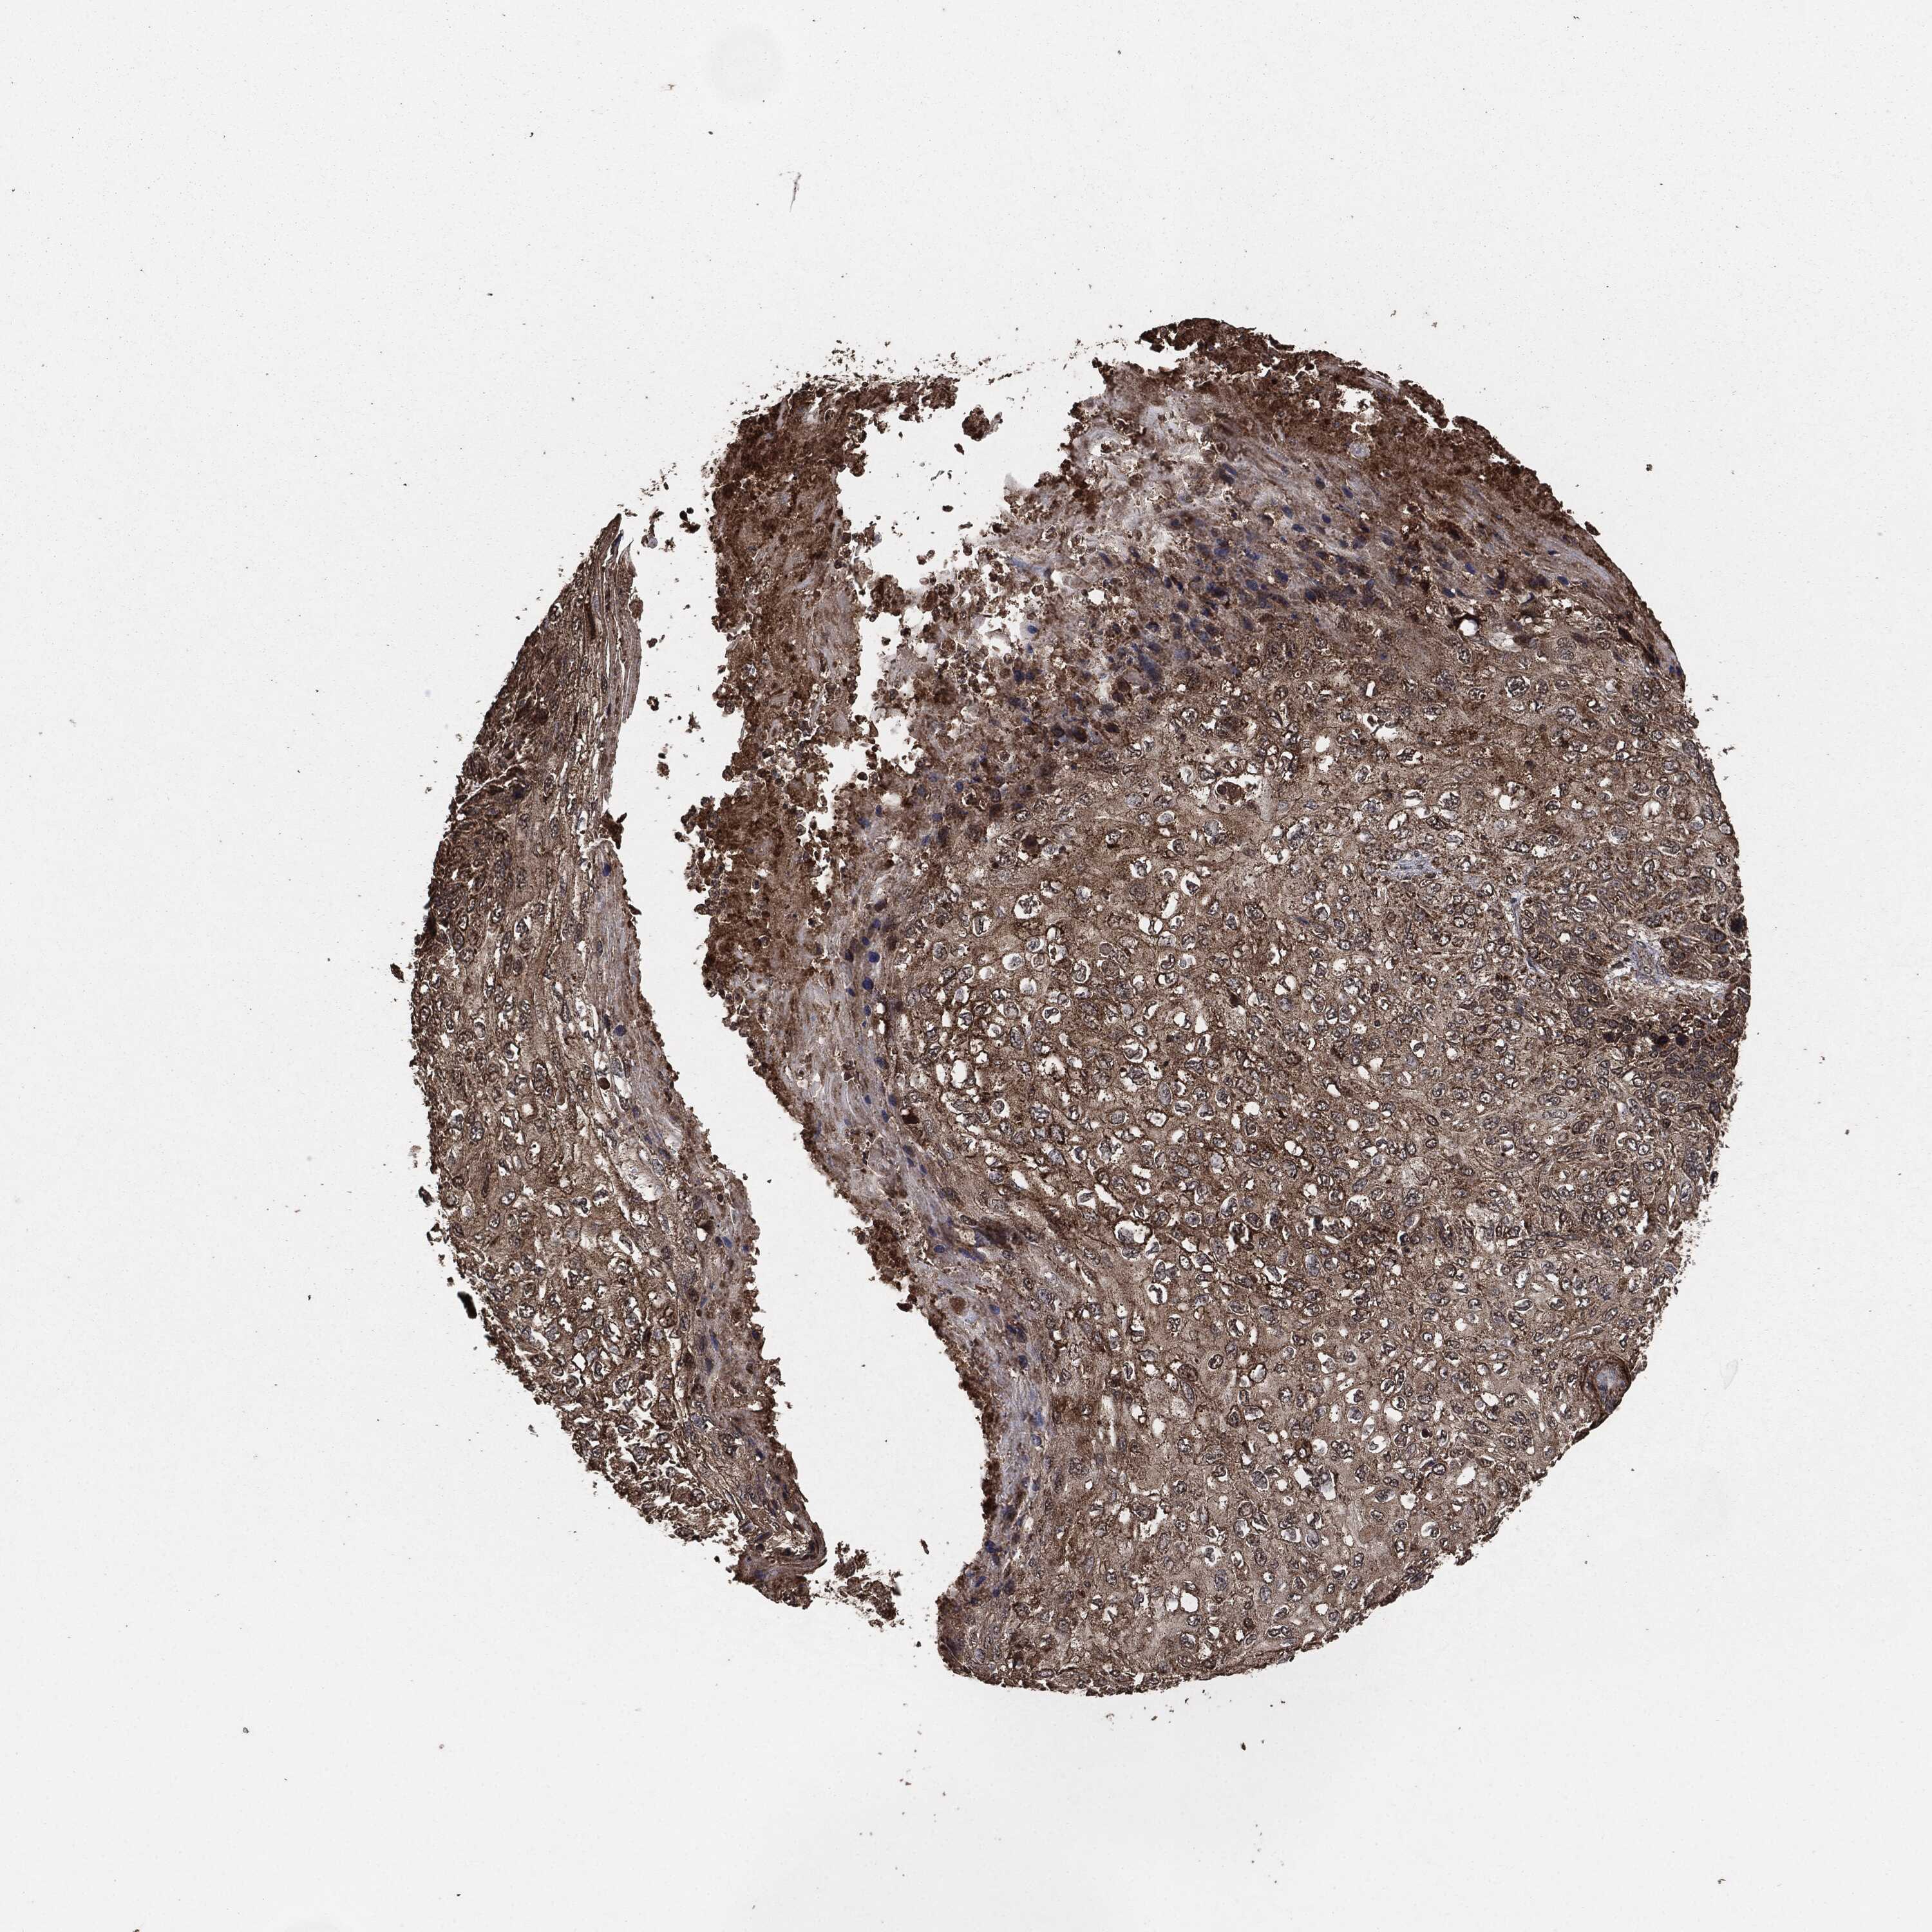

SKIN CANCER - Protein expressioni

A mouse-over function shows sample information and annotation data. Click on an image to view it in a full screen mode. Samples can be filtered based on level of antibody staining by selecting one or several of the following categories: high, medium, low and not detected. The assay and annotation is described here.

Antibody stainingi

Antibody staining in the annotated cell types in the current human tissue is reported as not detected, low, medium, or high, based on conventional immunohistochemistry profiling in selected tissues. This score is based on the combination of the staining intensity and fraction of stained cells.

Each image is clickable and will lead to virtual microscopy that enables deeper exploration of all samples and also displays staining intensity scores, fraction scores and subcellular localization as well as patient and tissue information for each sample.

Squamous cell carcinoma, NOS